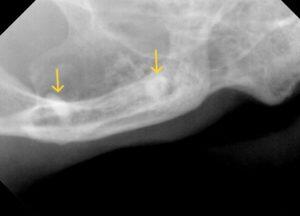

レントゲン検査では、

右上顎臼歯の残根2本と下顎臼歯の残根1本、犬歯は歯冠切除を実施していましたが歯肉に近い場所でした。

レントゲンで確認できる残根を抜歯し、下顎犬歯はより深い場所で切除を実施しました。